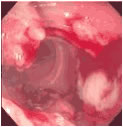

근래에는 식생활이 서구화 되어감에 따라 예전에 비하여 대장 직장암의 발생률이 증가되어 가고 있는 추세로 최근의 조사에 따르면 우리나라에서 남녀 공히 네 번째로 많은 암이며 조기에 치료하면 완치가 될 수 있는 병이기에 대장, 직장암에 대한 올바른 이해가 중요합니다. 병리학적으로는 대부분이 선암(adenocarcinoma)이며, 부위별로는 크게 결장암과 직장암으로 구분됩니다. 부위별 발생빈도는 하부 대장, 즉 직장에서 발생하는 경우가 약 50%로 가장 많습니다.

직장에 암이 발생하였을 때는 증상이 비교적 특이하여서 붉은색을 띄는 선혈 또는 점액이 섞인 붉은 피가 대변에 섞여 나오고, 대변보기가 힘들고, 대변이 시원하게 나오지 않기 때문에 변소를 자주 다니게 되고, 대변을 보고 나서도 시원하지 않은 느낌을 갖게 됩니다. 이런 증상이 있을 때 대부분은 쉽게 지나치게 되는데 이것이 완치의 기회를 놓칠 수 있으므로 이런 증상이 있으면 일단 조기 발견을 위한 노력이 필요합니다.

대장과 관련된 증세를 보이는 환자에게 직장 수지 검사(rectal digital exam), 분별 잠혈검사(stool occult blood exam), 대장조영술이 필수적이며, 필요에 따라 S상 결장경 검사 및 대장내시경검사를 통한 조직검사가 행해집니다. 최근에는 조기진단 목적으로 흔히 CEA 수치검사(chorioembrionic antigen) 및 분별 잠혈검사가 널리 이용되고 있습니다.